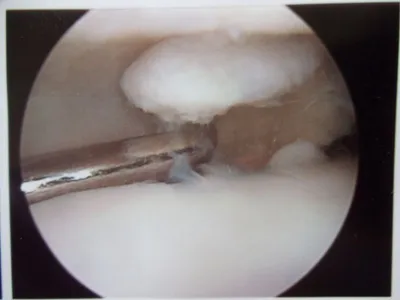

Pic during microfracture of tibial OCD.

Pics of nodules removed during scope.  A separate incision had to be made to remove the nodules due to the size.